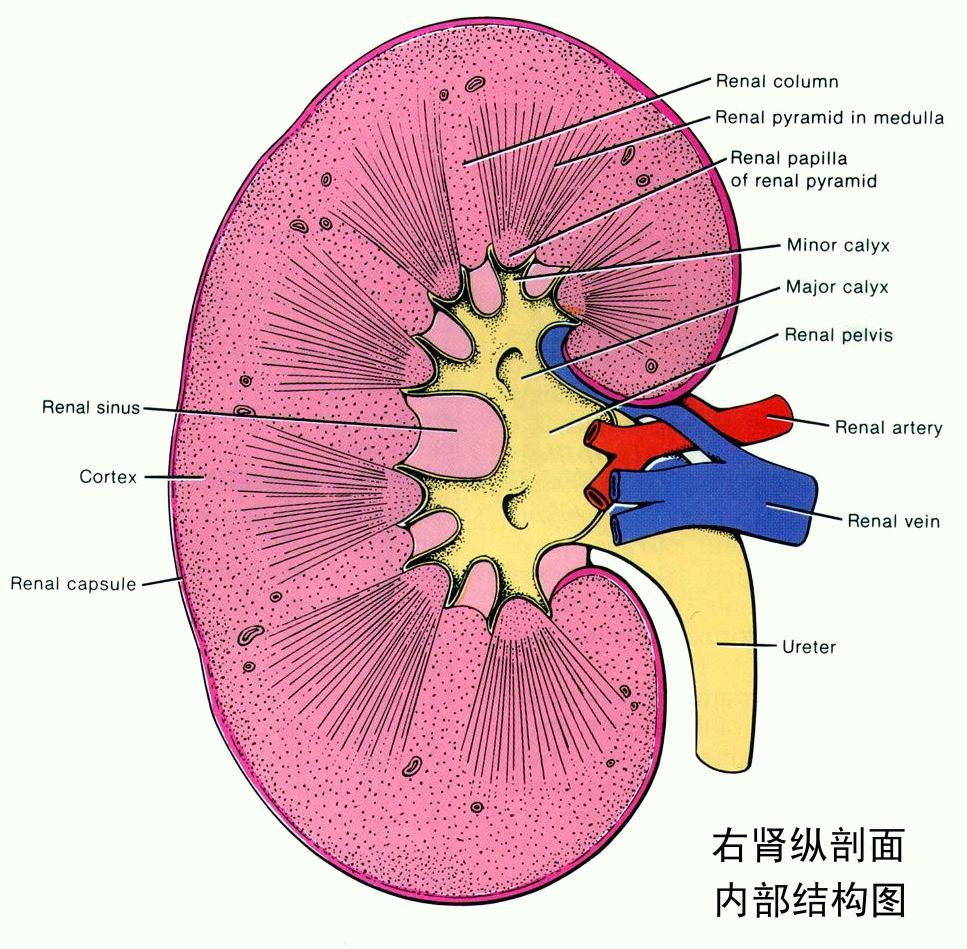

肾脏的形态像一颗蚕豆,内侧呈袋状向内凹,像一个钱包,称为肾窦(Renal sinus)。肾实质包绕肾窦,超声上显示肾实质光点亮度较低,肾窦光点亮度明显增高,位于中央呈椭圆形,内包括肾盂(Renal pelvis)、肾盏(Renal calyx)、血管等。肾盂、肾盏与输尿管(Ureter)相通。

1、肾积水:如果肾盂肾盏内含有液体时,肾窦中间出现无回声区。正常情况下,无回声区的前后径不超过1.5cm,若超过2cm时,一般诊断为肾积水。肾积水多由尿路梗阻造成,尿路梗阻的原因有结石、肿瘤、前列腺增生、输尿管狭窄等,这些都可以通过超声检查发现。

2、肾结石:如果在肾盂肾盏内出现沙砾状或小块状强光团,基本可诊断为肾结石。如果结石在肾脏内不移动,一般是没有明显症状的,但如果结石脱落进入输尿管,输尿管会受结石刺激而产生痉挛,这样就会引起绞痛而出现明显症状,有时会伴有血尿出现。有症状的肾结石虽然很痛苦,但不会危及生命,所以不用太紧张,一般可通过体外碎石或口服排石药物来治疗。如果你想了解更多肾结石相关的内容,可以看看我们之前的文章:肾结石的病因有哪些?有什么临床表现?如何检查?

5、肾肿瘤:肾肿瘤以恶性占大多数,又分为肾实质肿瘤和肾盂肿瘤两类。肾实质肿瘤在超声上表现为肾局部隆起,外形异常,病变成圆形或椭圆形。肾癌早期病人往往没有明显症状,一旦出现血尿、腹痛、腹部肿块等症状时,说明肿瘤已经很大了。所以定期肾脏B超检查是早期发现肾癌最主要的手段,建议40岁后每年做一次肾脏B超检查。肾盂肿瘤的声像图特点是:在肾窦区出现占位性病变,使肾窦扩大,这类患者多伴有血尿,所以一般发现比较早。